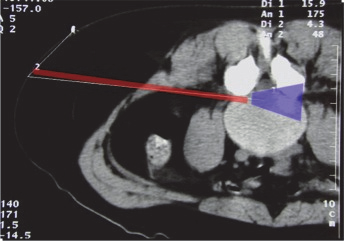

It is the “Kambin triangle” (the safe corridor to the lumbar disc between the exiting nerve root and the superior facet) which reminds us of his pioneering work (Figure 9).

Figure 9: Kambin’s triangle for a safe posterolateral approach.

This lateral extraforaminal approach enabled the removal of far lateral disc herniations as well as more medially located pathologies because the approach corridor was more parallel to the posterior rim of the annulus (Figure 11).

Figure11: Approach corridor and visual field for transforaminal approach.